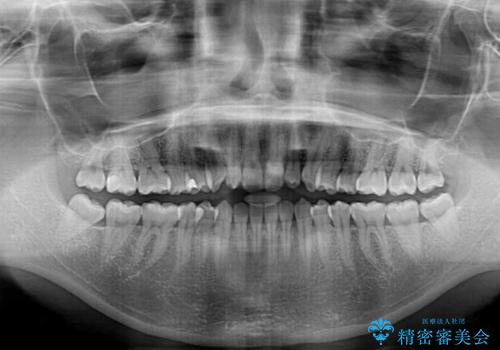

- 上顎前歯の叢生を気にして来院された患者様です。

下顎前歯や上下奥歯の咬み合わせには殆ど問題がないため、上顎前歯のみを矯正する治療を提案しました。